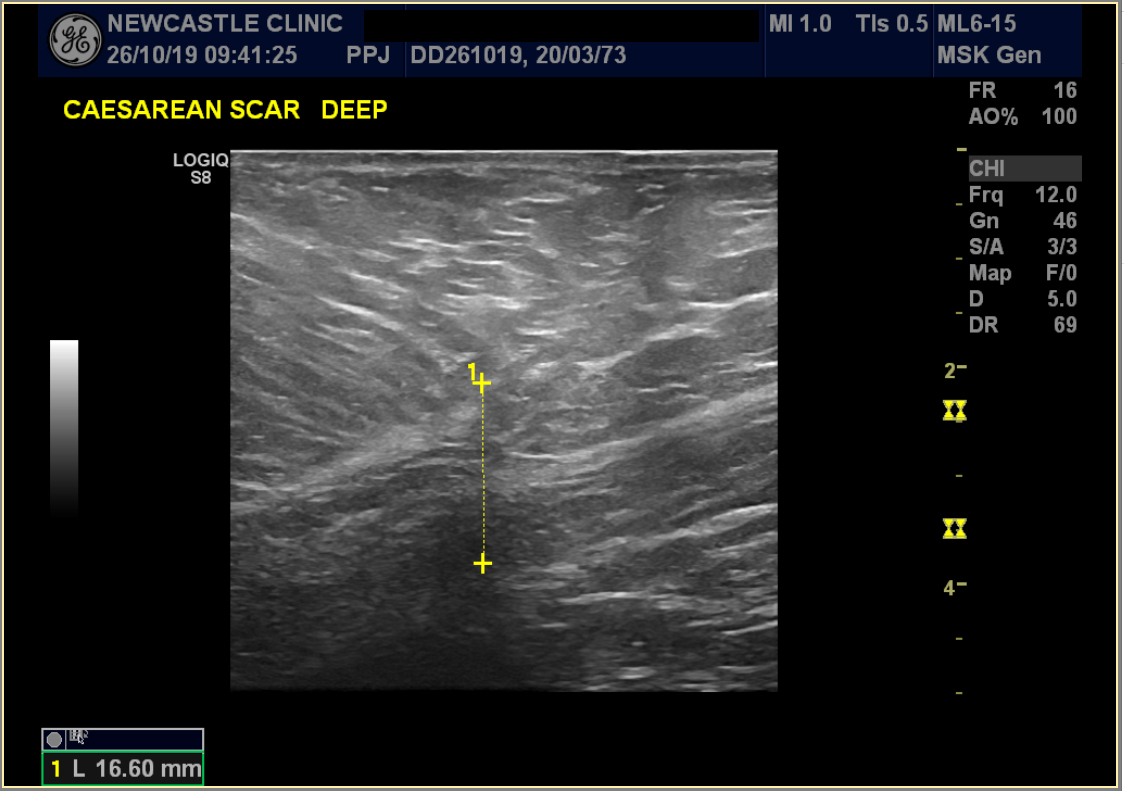

Ultraljudsbilder

Det här kejsarsnittsärret var 16,6 mm djupt innan behandling.